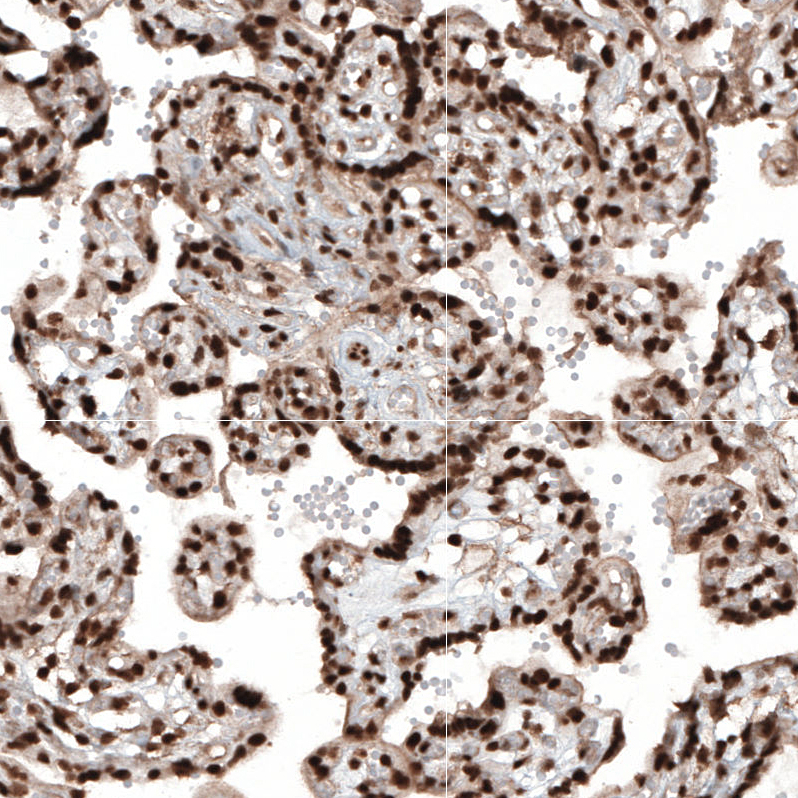

Immunohistochemical staining of human cerebral cortex shows moderate to strong nuclear positivity in neuronal cells.